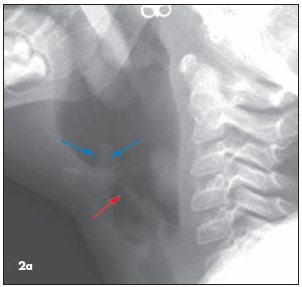

Epiglottitis. (Figure 2a) Recall that the child's home environment does not seem to be especially good. Thus, immunizations might not be up-to-date, and ingestion or inhalation of toxic chemicals in or around the home is a possibility (the latter could cause airway compromise or even inflammation of the epiglottis). Thus, even though epiglottitis would be unlikely, it is wise to make sure you can rule it out. Fortunately, the radiographs show the epiglottis (blue arrows) to have a normal, slender contour; they show the aryepiglottic folds (red arrow) to be normal as well-and thin. These findings rule out epiglottitis.

Mass. This is the correct answer. On the lateral view, a lobulated soft tissue mass can be seen arising from the posterior wall of the upper hypopharynx (Figure 2c). The mass is approximately 2 cm cephalocaudal by 1 cm anteroposterior, and its edges form acute angles with the hypopharyngeal wall (oblique angles would be expected if this were extrinsic to the airway and deforming the hypopharynx from the outside [Figure 2d]). This mass is an unexpected and abnormal finding; its differential diagnosis includes hemangioma, polyp, granuloma, foreign body (although not in the esophagus because the mass forms acute angles with the pharyngeal wall), and papilloma.